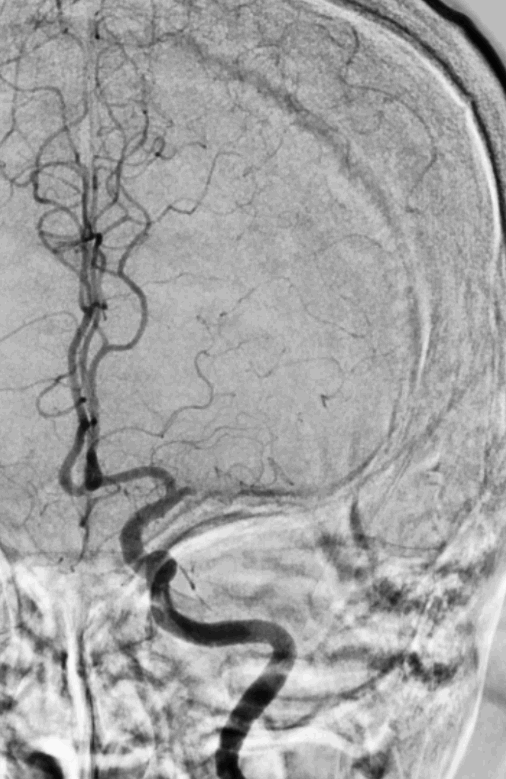

术前造影提示:左侧大脑中动脉闭塞,可见部分豆纹动脉显影,左侧大脑前动脉通过脑膜支代偿左侧大脑中上干。

中年男性患者,起病急,病情有进展加重表现,造影提示左侧大脑中动脉近端以远闭塞,大脑前部分代偿,造影闭塞为椎形征,考虑脑梗死发病机制为ICAS可能性大。拟行“BASIS技术”取栓及开通左侧大脑中动脉闭塞必要行支架植入术治疗。

再次将4.0*30mm Syphonet®取栓支架释放到位并造影,见左侧大脑中动脉狭窄段仍明显,且靠近豆纹动脉处。

考虑狭窄明显并夹层形成,遂行4.5*22mm 自膨式闭环支架于左侧大脑中动脉水平段并造影。

最后路径手推造影,造影确认脑血流完全恢复,mTICI 3级。